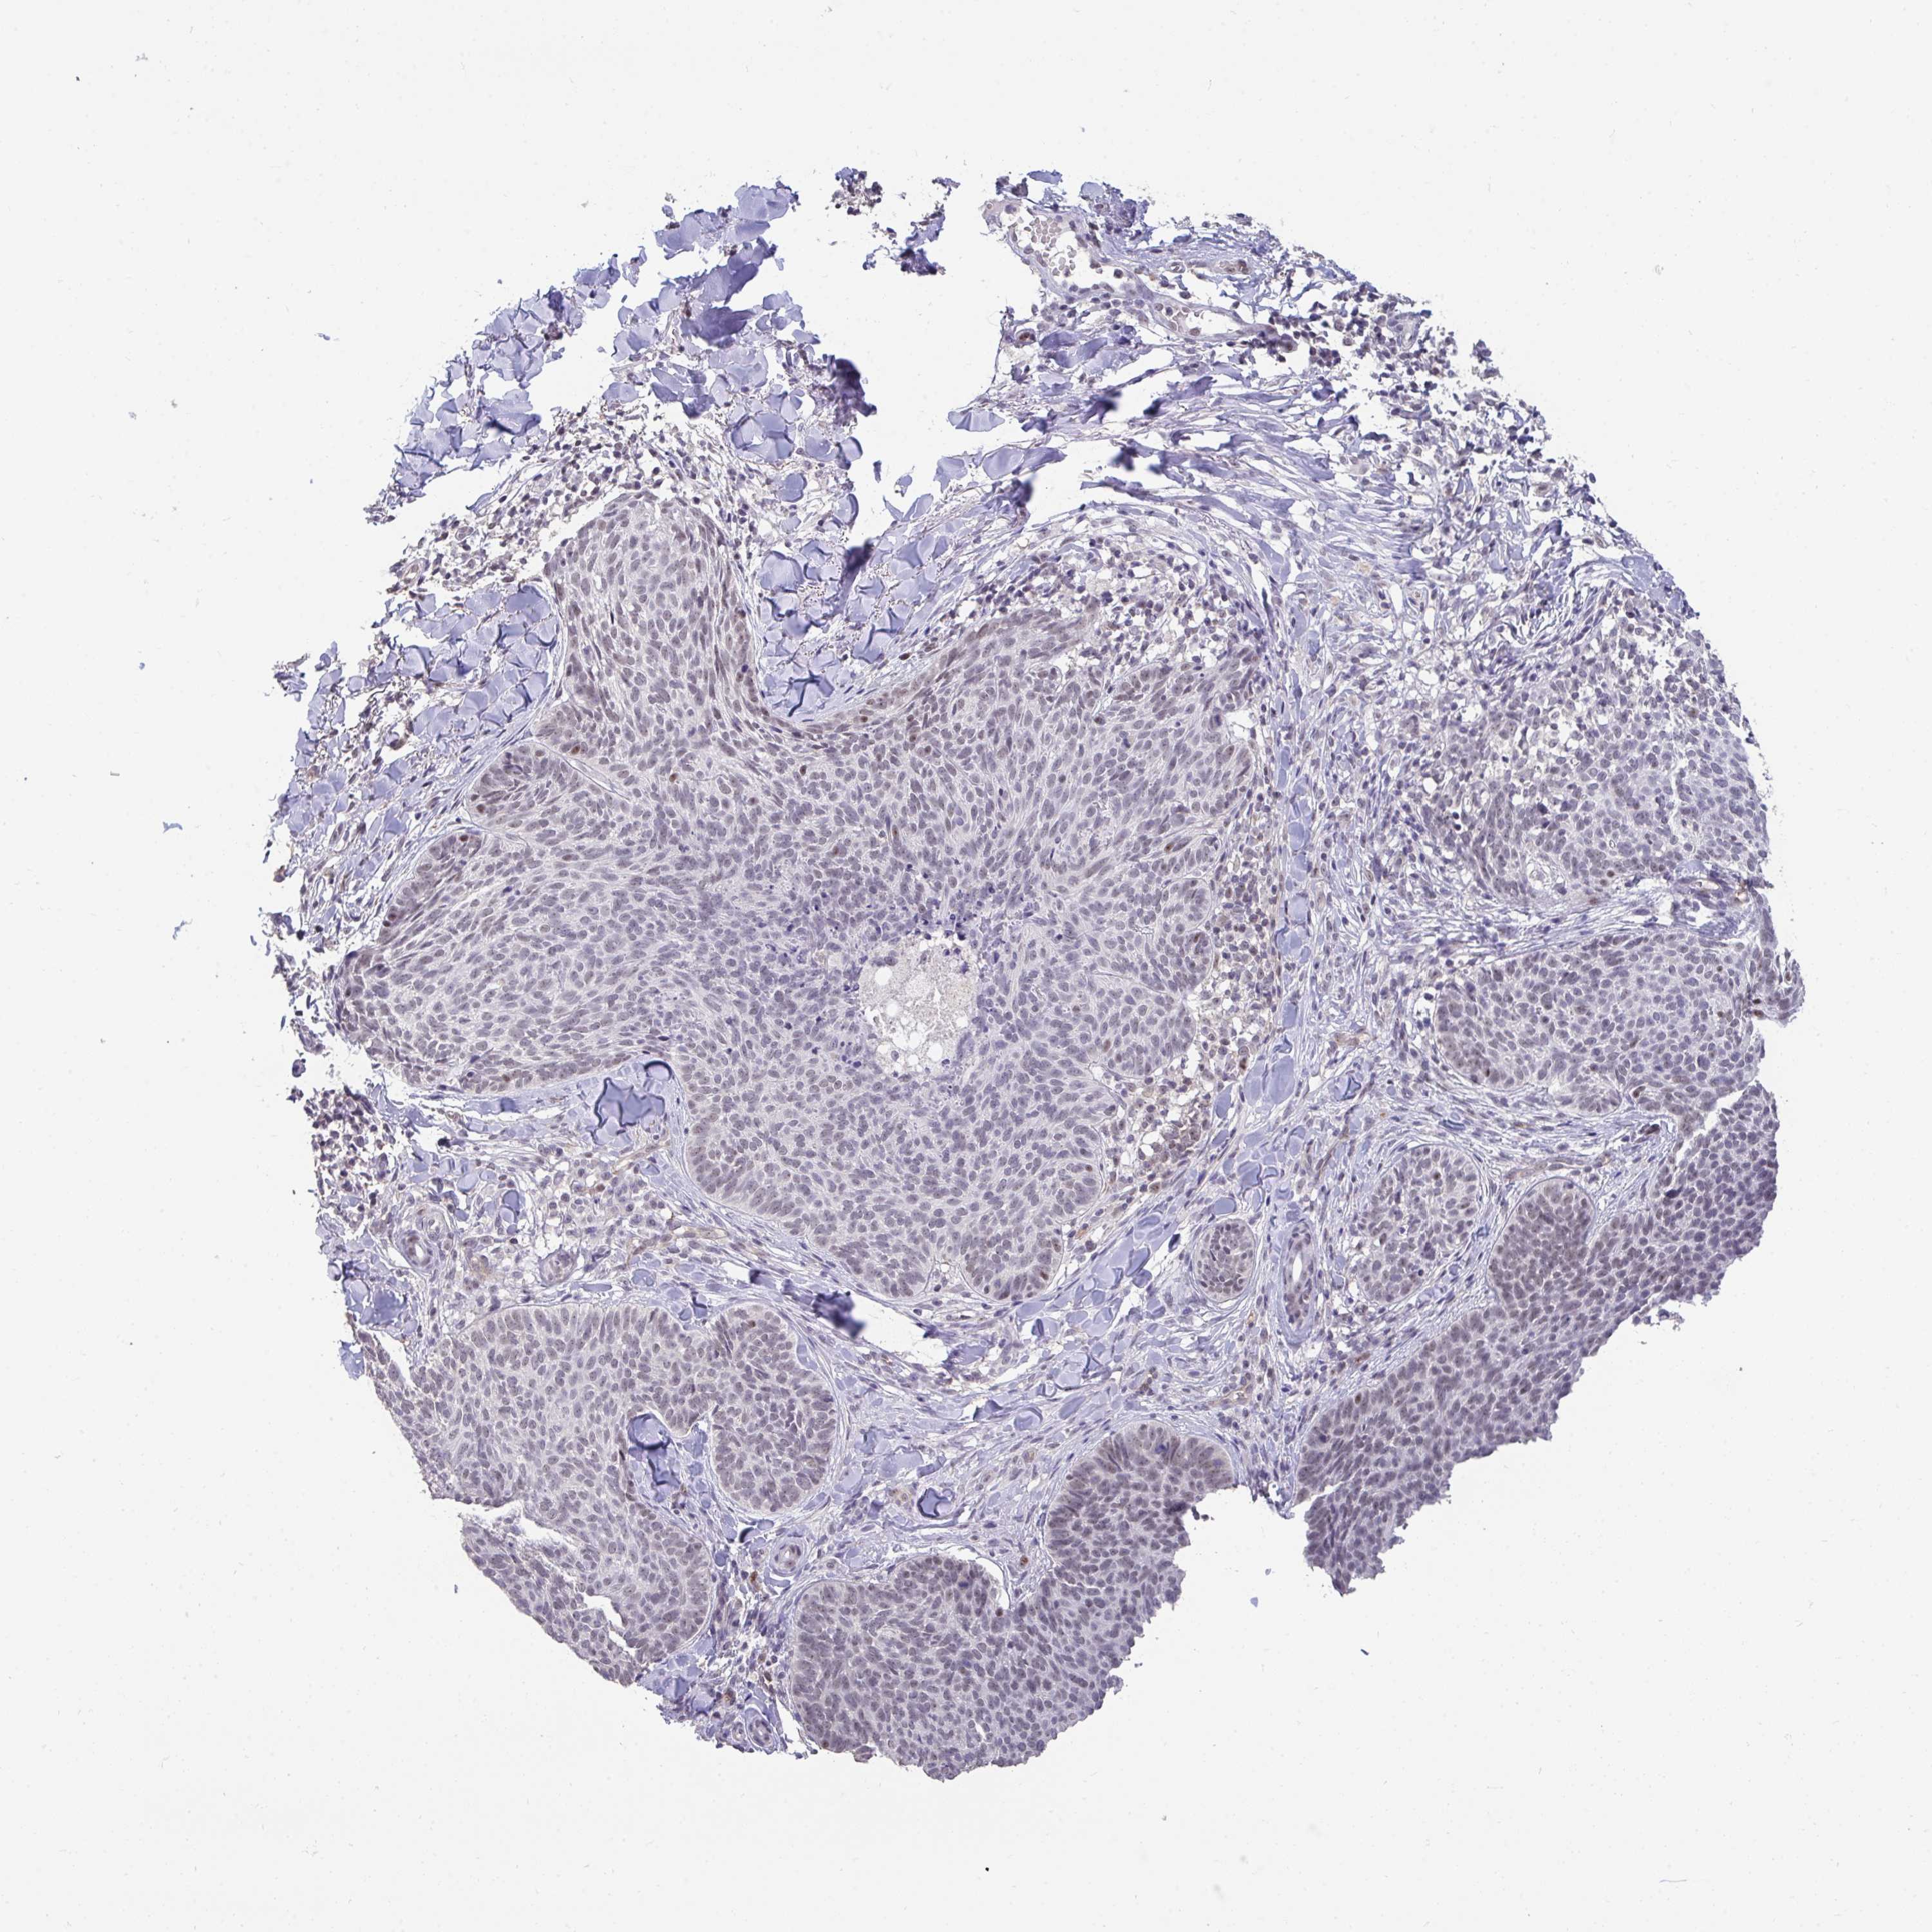

SKIN CANCER - Protein expressioni

A mouse-over function shows sample information and annotation data. Click on an image to view it in a full screen mode. Samples can be filtered based on level of antibody staining by selecting one or several of the following categories: high, medium, low and not detected. The assay and annotation is described here.

Antibody stainingi

Antibody staining in the annotated cell types in the current human tissue is reported as not detected, low, medium, or high, based on conventional immunohistochemistry profiling in selected tissues. This score is based on the combination of the staining intensity and fraction of stained cells.

Each image is clickable and will lead to virtual microscopy that enables deeper exploration of all samples and also displays staining intensity scores, fraction scores and subcellular localization as well as patient and tissue information for each sample.

Antibody HPA060290

Staining

High

Strong

Quantity

Location

Basal cell carcinoma

Squamous cell carcinoma, NOS